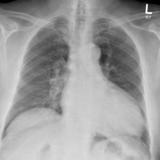

Aortic aneurysm

Date: 03/02/2014

Views: 2132